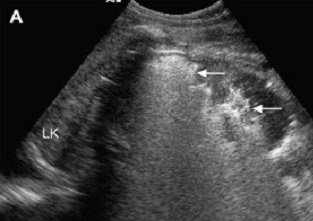

Renal ultrasound Renal infarct: